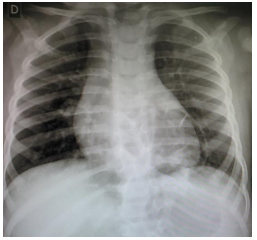

Menina de 1 ano apresenta tosse e coriza nasal hialina há 5 dias, sem febre. Exame físico: bom estado geral, frequência cardíaca de 120 bpm, frequência respiratória de 38 irpm, murmúrios vesiculares presentes e simétricos, com roncos transmitidos de vias aéreas superiores difusos. Antecedentes pessoais: 2 episódios de pneumonias tratadas ambulatorialmente, com 6 meses e 9 meses de idade. Raio x de tórax: imagens a seguir:

Enunciado 3405859-2